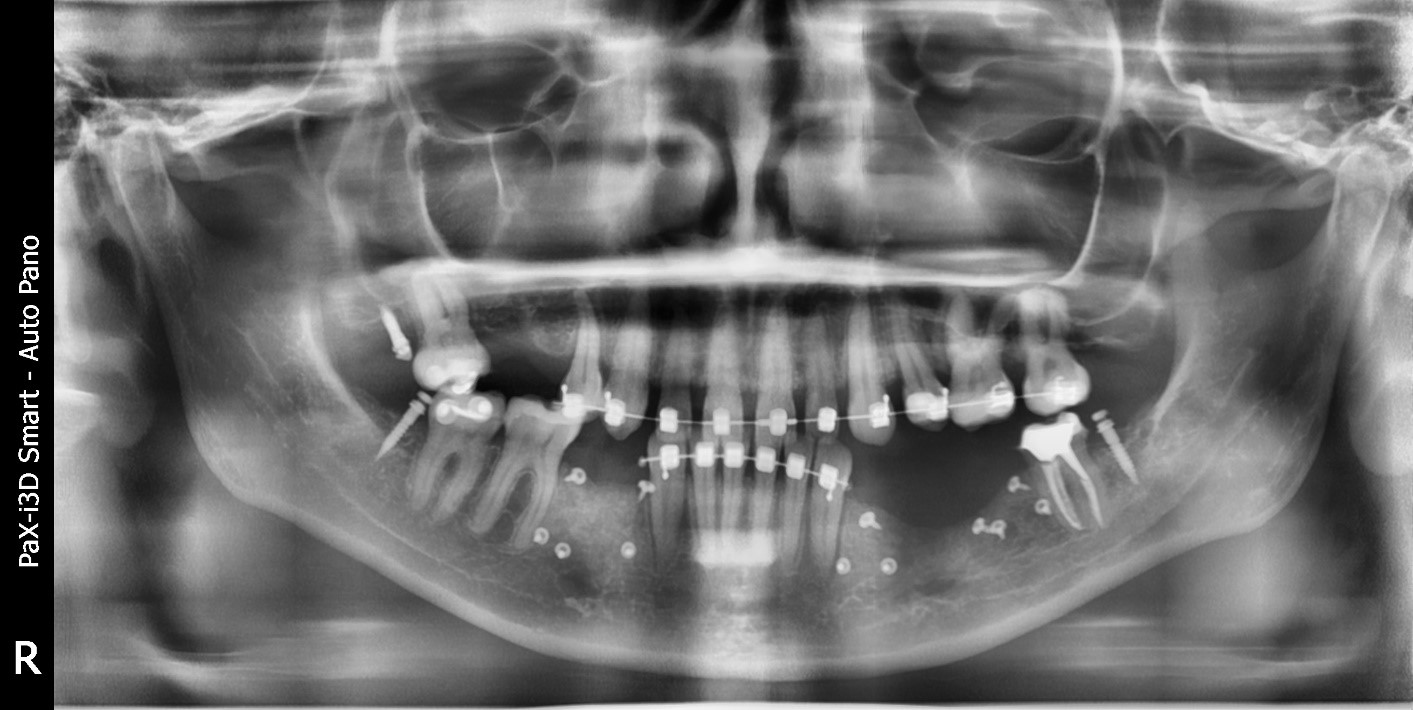

2024-06-06 в 11:00, admin, рубрики: здоровье, зубы, клиника, лечение, пациент, стоматологияСергей, технический директор ИТ-компании, пришёл к нам с весьма характерной историей и классической картиной «рта айтишника». У него были абсцесс, стёртые жевательные зубы, сильный запах изо рта и стоматофобия. Но больше, чем стоматологов, он боялся бросить лечение на середине пути, как уже бывало в прошлом.

Собственно, даже на рентгене видно, что наши коллеги когда-то давно лечили Сергея не очень хорошо

До «Белой Радуги» моё знакомство с карательной советско-российской стоматологией выглядело так: кругом — мышьяк, и в борьбе с пульпитом убивались все зубы, до которых можно было дотянуться. После этой «бережной» процедуры оставшиеся без нервов зубы методично разрушались и крошились, пока вместо жевательных зубов не оставались только острые обломки, о которые я постоянно резал язык. Правда, надо отметить: мой «фасад» до упора выглядел довольно неплохо, и после лечения улыбка внешне почти не изменилась. Но если я улыбался слишком уж широко, то в одном месте было видно золотую коронку, а в другом — большой провал. Жевательных зубов у меня почти не осталось. К тому же, честно говоря, с гигиеной всё было отвратительно, и изо рта у меня сильно пахло. Усугублял положение тот факт, что в последние 18 лет я много курил, и это тоже не добавляло дыханию свежести.

Изначальный запрос выглядел так: «Нет сил это терпеть, снесите мне все зубы и сделайте вставную челюсть». Сразу скажем, что получил он совсем не это.